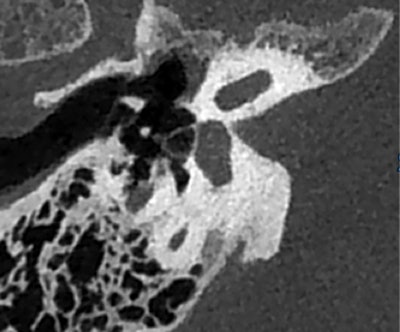

Jusqu'ici, alors que les CBCT dentaires et sinusiens font partie des examens remboursés, les CBCT de l'oreille ne le sont pas, bien que cette modalité surpasse la tomodensitométrie pour analyser de petites structures telles que l'étrier. Le CBCT de l'oreille est très utile pour la planification pré-chirurgicale de l'oreille moyenne et pour la visualisation du positionnement des implants cochléaires, selon le Pr Francis Veillon, professeur d'imagerie à l'Université de Strasbourg et chef du département d'imagerie viscérale et ORL dans ce CHU.

"Les excellents résultats obtenus par le CBCT en font un outil indispensable pour les patients malentendants. Ne pas l'utiliser coûte plus cher", a déclaré le Pr Veillon à l'auditoire lors de la journée de formation pré JFR. "Le CBCT joue un rôle crucial dans l'évaluation des patients à opérer ou non."